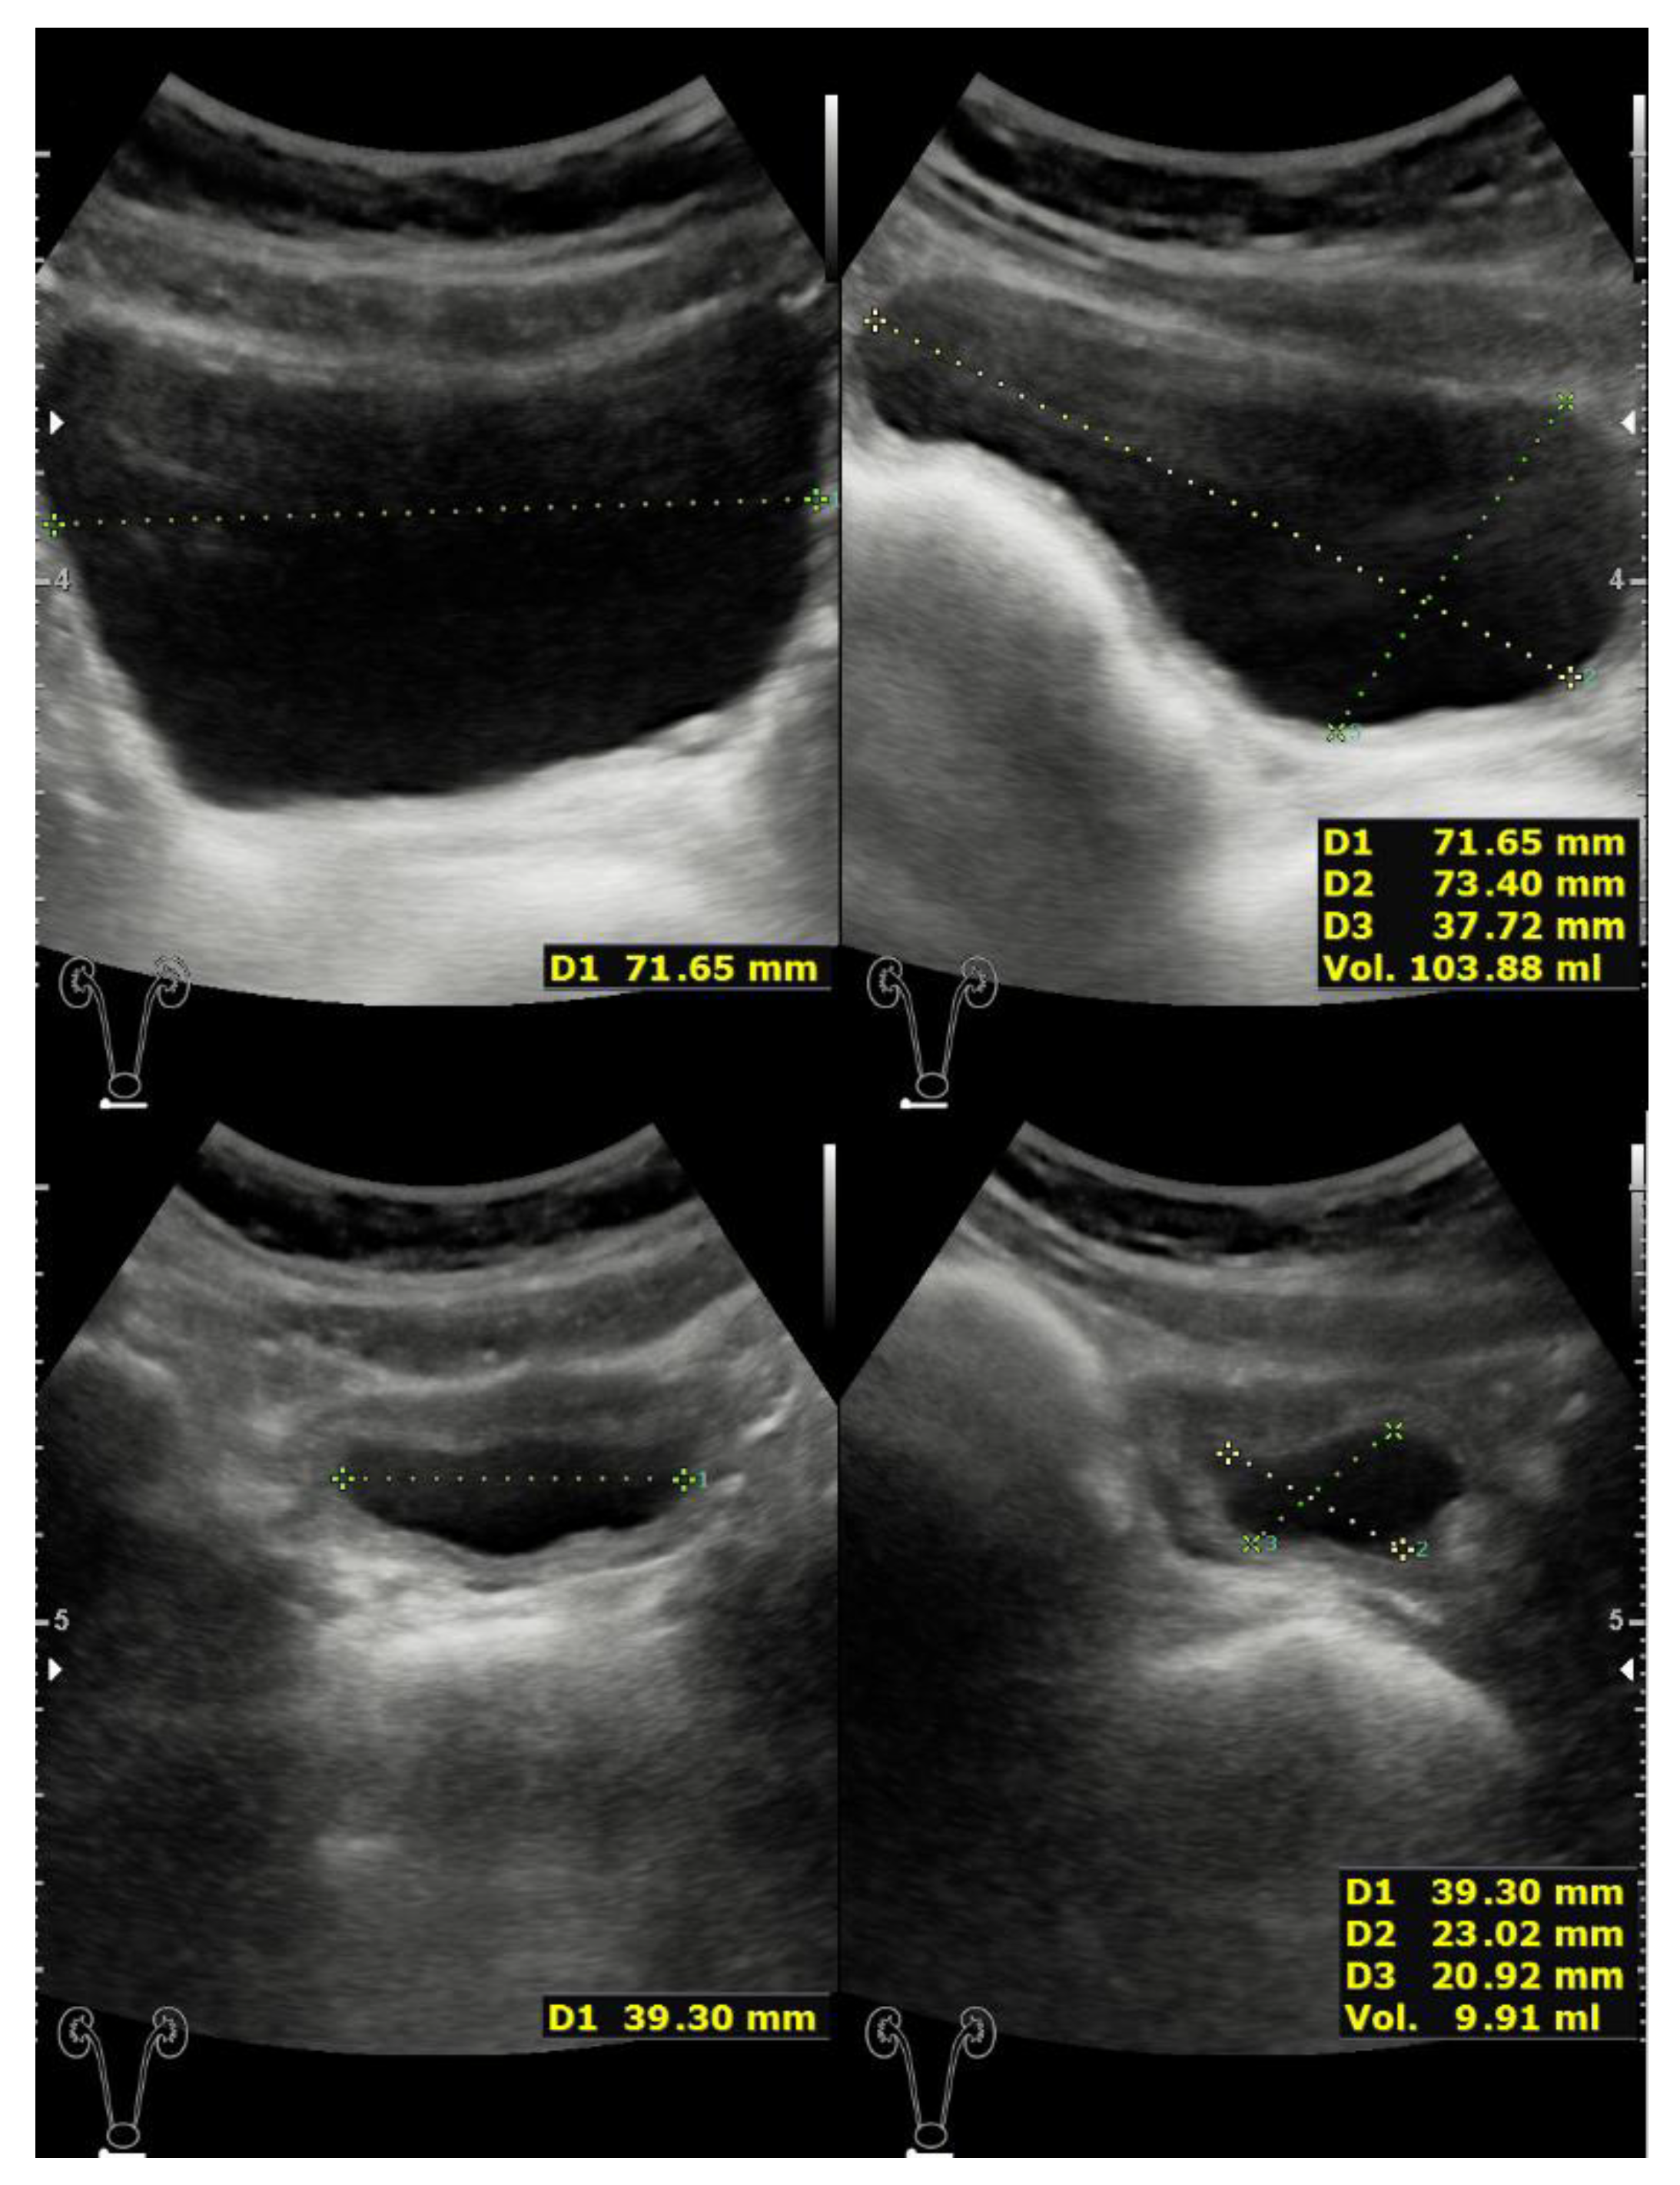

2.2. Case 2